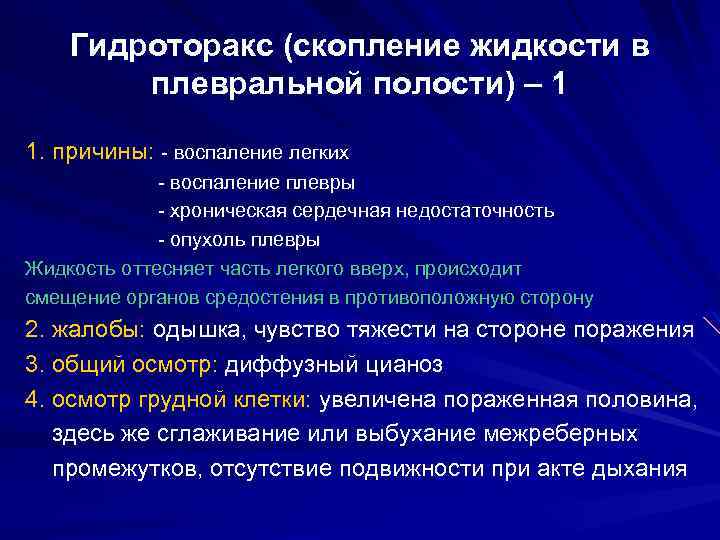

Диагностика плеврального выпота: что нужно знать